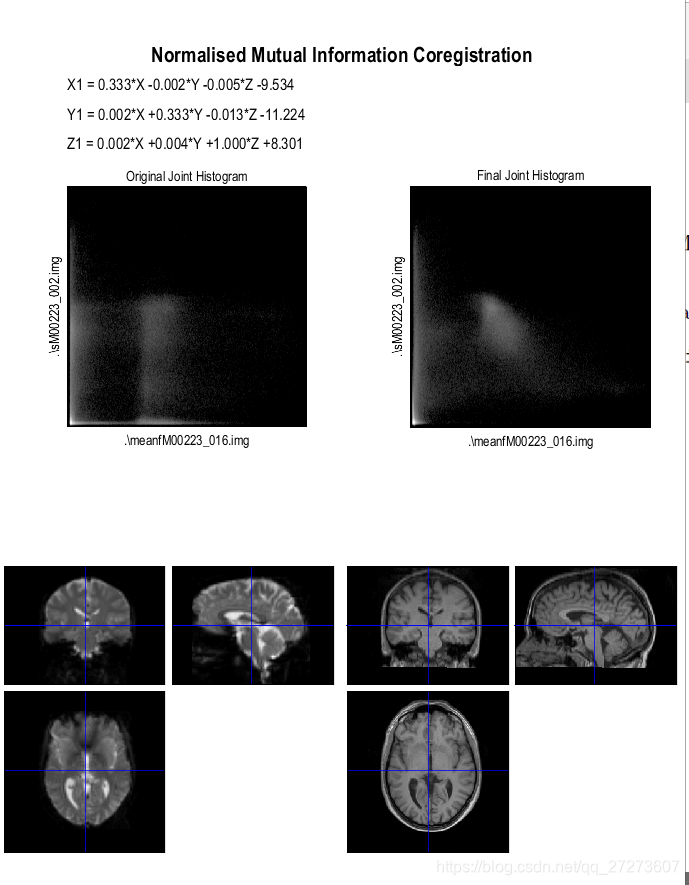

2.2 Coregistration配准

在fmr初始界面选择Coregister,然后按照如下指令操作。

SPM将在结构像数据和功能像数据建立起关联,